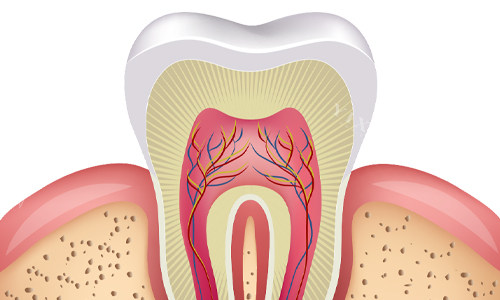

富源昆口牙院长口腔医院的特色项目包括牙齿种植、牙齿矫正、儿童齿科、常规治疗等。在种植牙领域,医院采用可靠的智能化种植技术,结合3D影像扫描和计算机辅助设计,能够正确定位种植体位置,确保手术的可靠性和成功概率。此外,医院还引进了瑞士ITI和德国ANKYLOS等高端种植系统,种植体质量可靠,术后成效稳定。